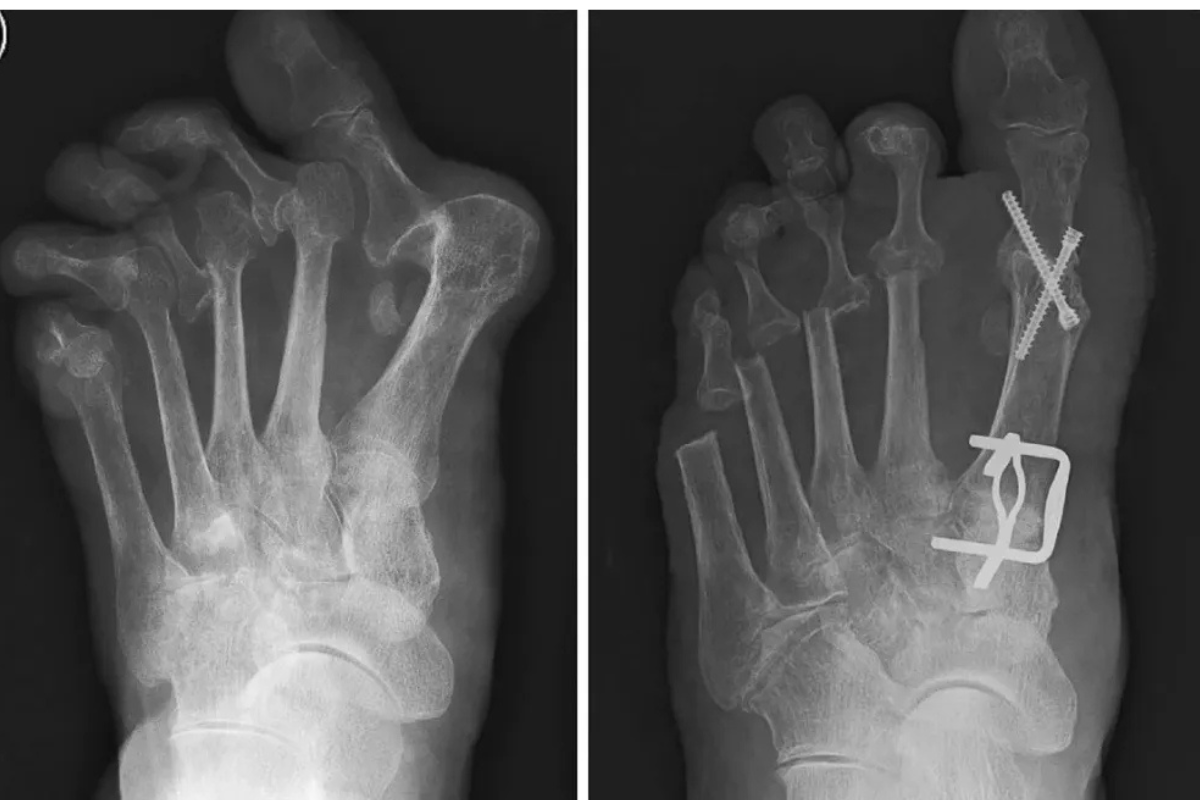

Specialized surgical care for Rheumatoid Arthritis and Polio to restore mobility and enhance function.